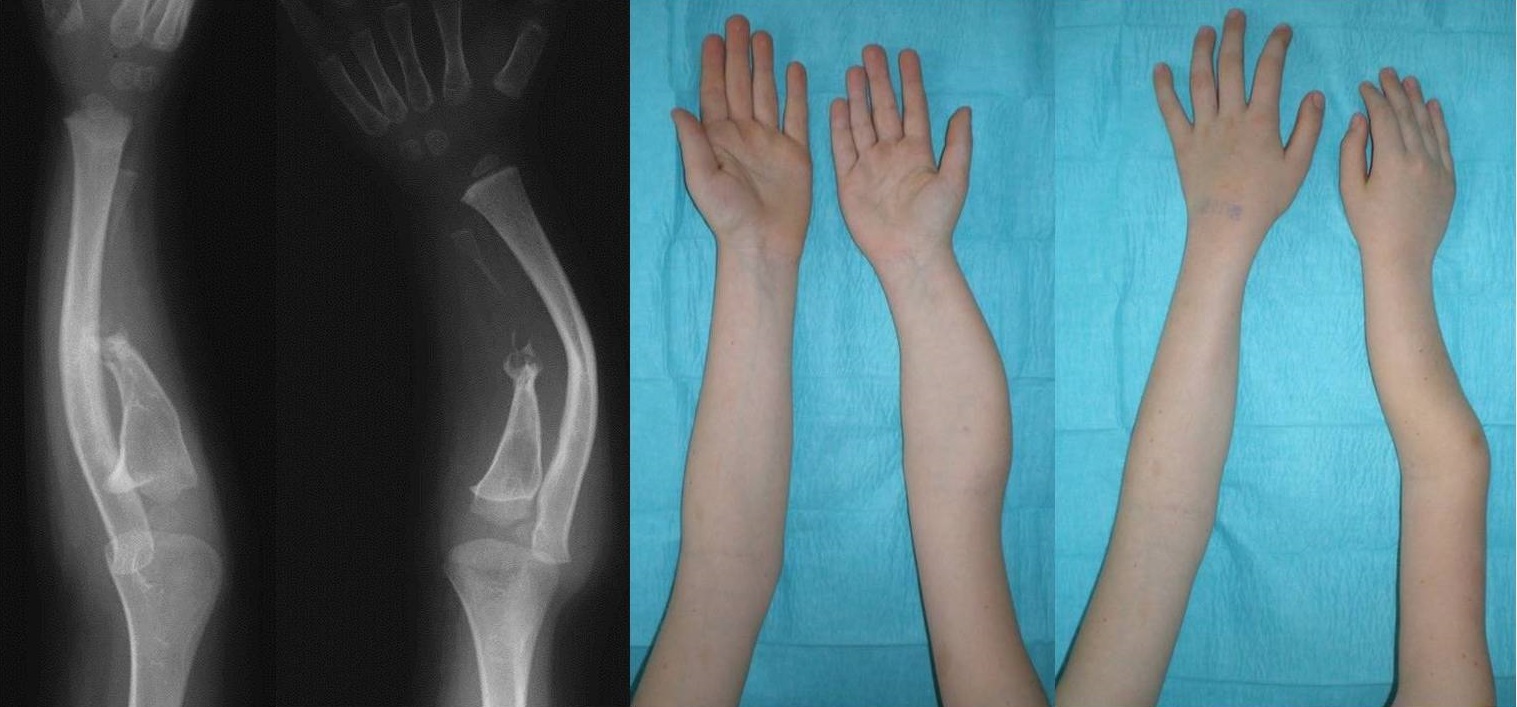

The sixth patient was a 9-year-old boy with shortening and bowing of the right forearm manifested at birth. There was a positive family history of NF1 in his mother, and the patient was also diagnosed with NF1. Congenital pseudarthrosis of the ulna with a dysplastic appearance and an absent distal ulnar diaphysis, radial and ulnar bowing, and radiohumeral dislocation were diagnosed on the radiographs of the affected upper limb. The patient had been treated conservatively. He was referred with a diagnosis of neglected ULD in a patient suffering from NF1.

Physical examination at our service showed no forearm tenderness, a stable wrist with no deficiencies of the wrist and hand, limited ipsilateral elbow flexion-extension and forearm rotation, scoliosis, and hyperpigmented lesions on his body consistent with café au lait macules of underlying NF1.

The radiographic follow-up evaluation showed pseudarthrosis of the ulna at its middle third and a tapering end of the proximal third, while the distal third presented as a thin intermittent sclerotic line with a residual distal meta/diaphysis and epiphysis. Marked bowing of the radius with proximal migration of the dislocated radial head was also evident. The final diagnosis was isolated congenital bowing-pseudarthrosis of the ulna with resorption of the middle diaphyseal third due to osteolysis in a patient with NF1 (Figure 6).

Figure 6. Congenital angulation-pseudarthrosis of the ulna with osteolysis in a boy with neurofibromatosis type 1. The radiographs were taken when the boy was 3 years old and the photographs when he was 9 years old.